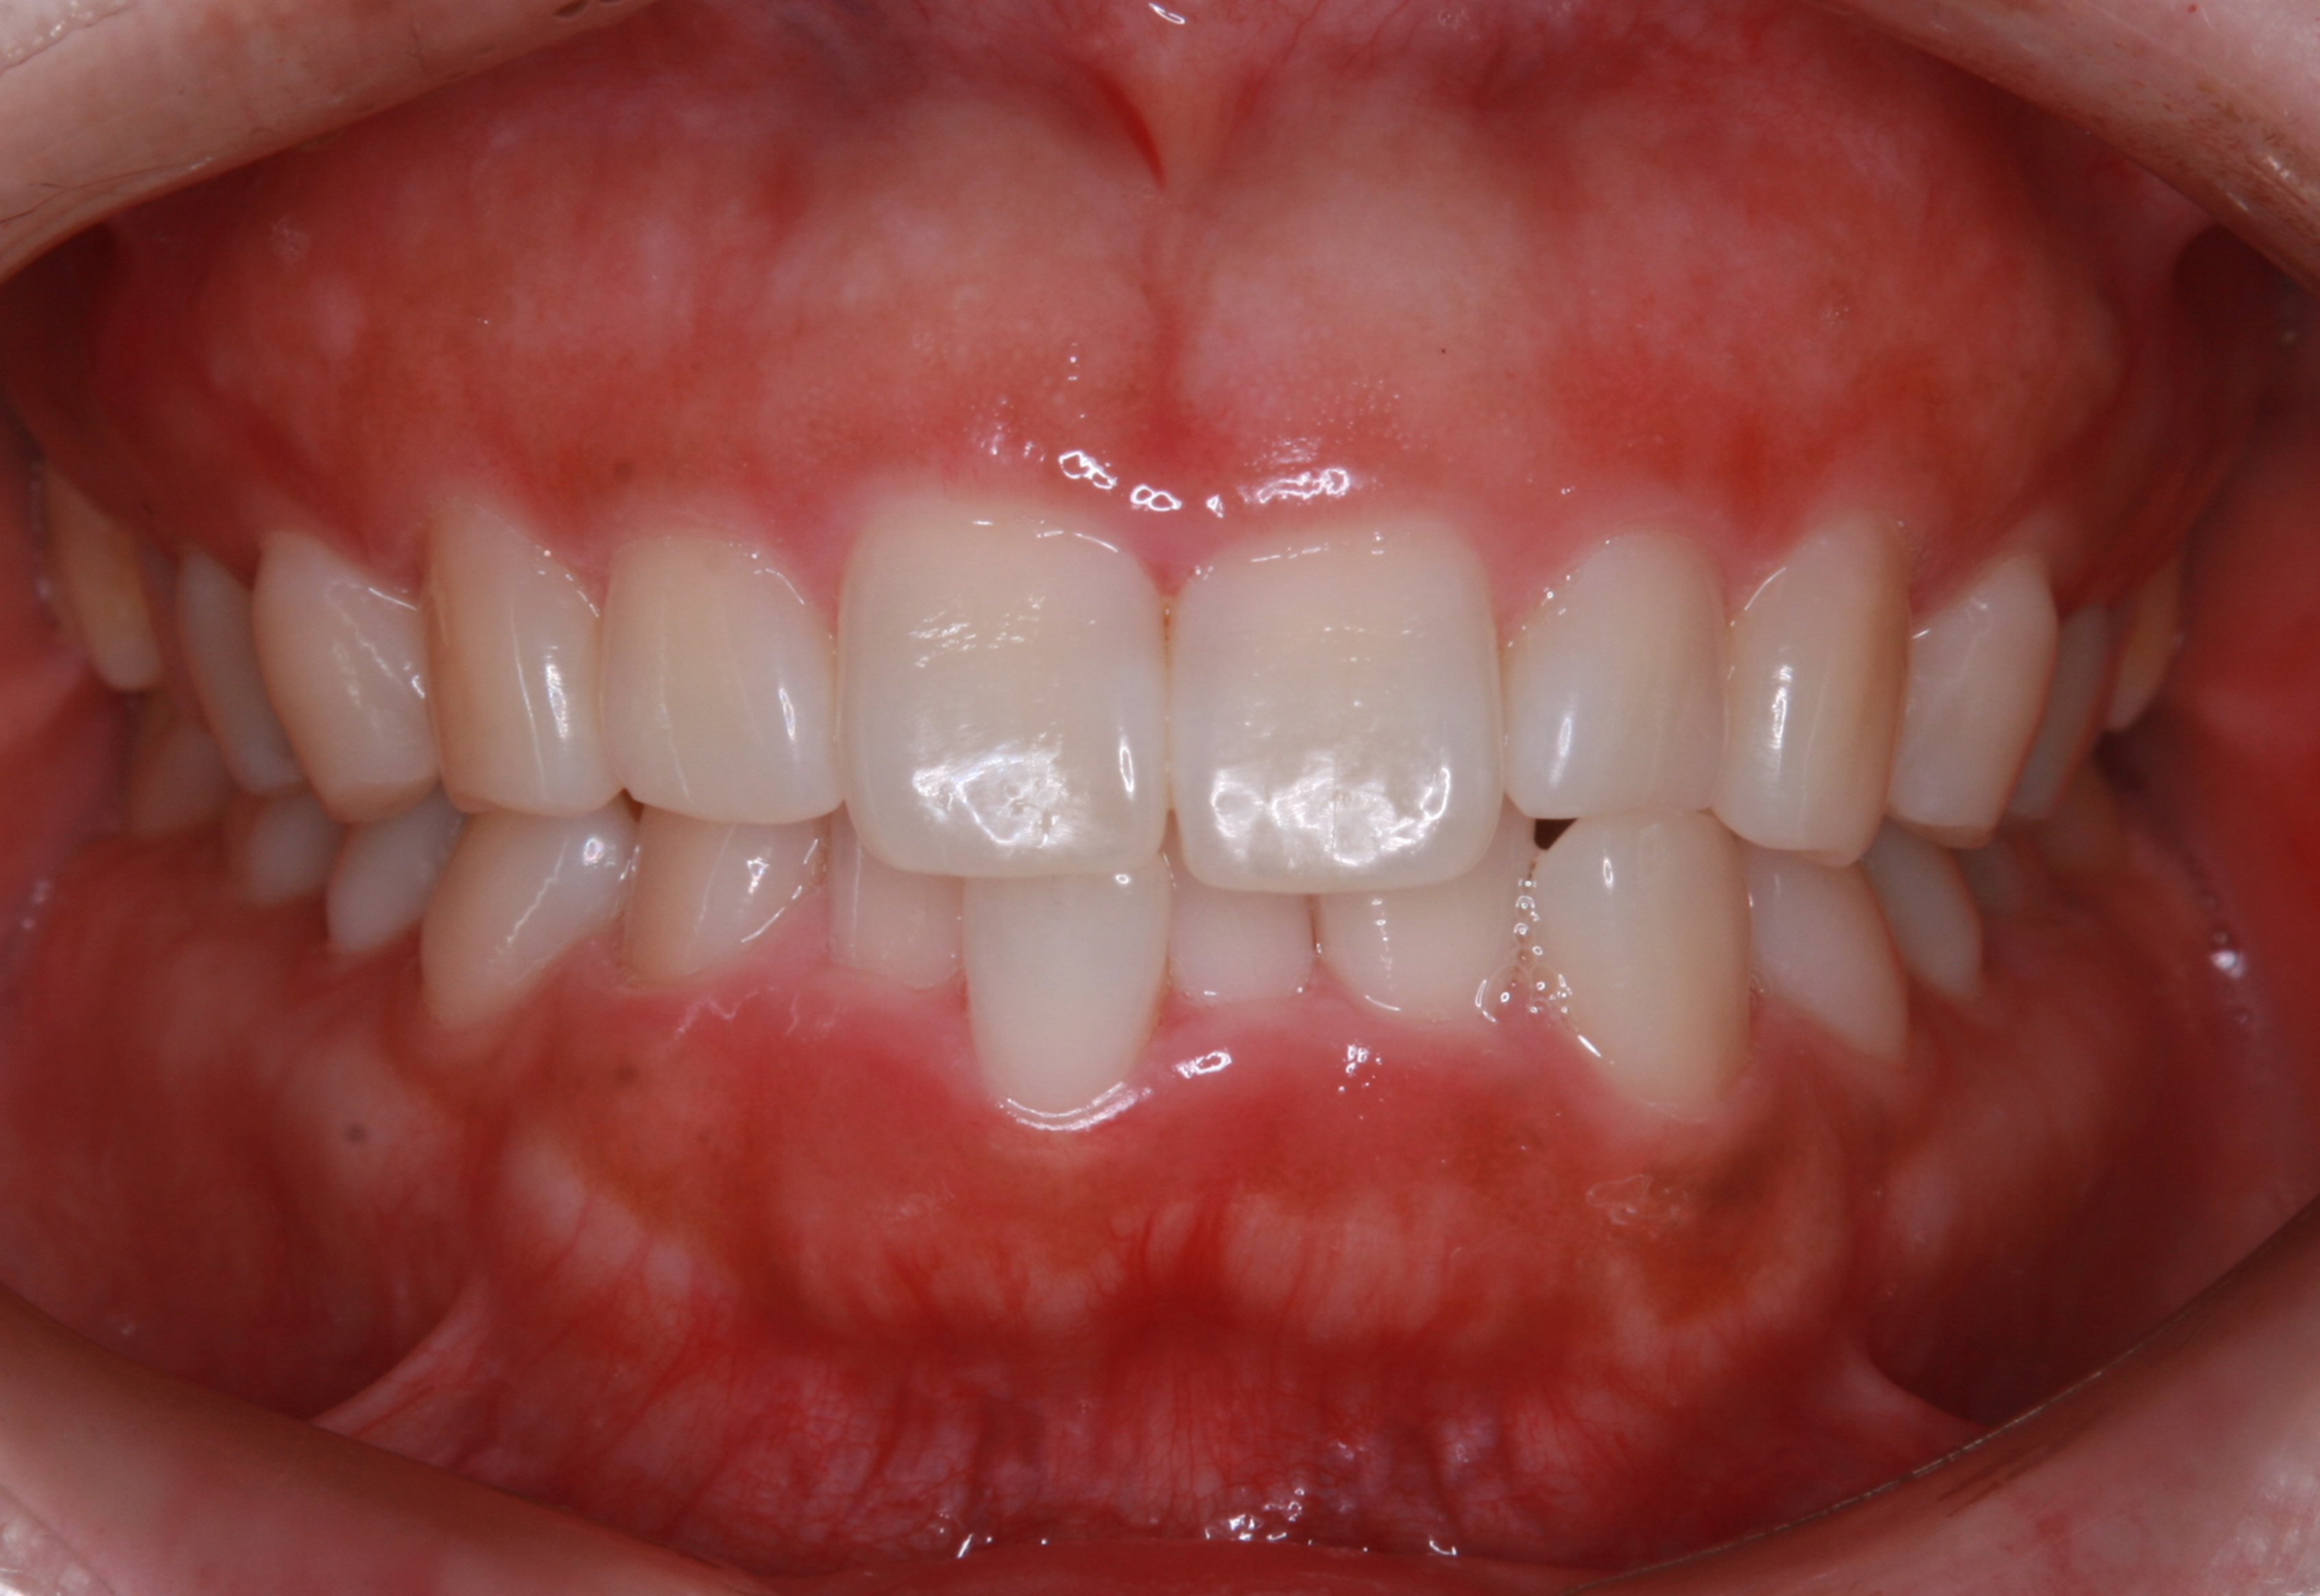

上顎前歯部の部分矯正

術前・術後の比較

治療の経過を表示する

-

患者の方は親知らずの痛みがあり当院にお越しになりました。幼少期から歯医者が苦手で、痛みがあってもなかなか行く勇気がでなかったそうです。笑気鎮静法を併用しながら、右下の親知らずを抜歯しました。

2024.6.25パノラマレントゲン写真

親知らずの痛みがなくなった患者さんは、昔から歯並びが気になっていることを打ち明けてくれました。特に上の歯が少し前に出ていたり、隙間があったりしている点を治したいそうです。そこで、まず上の歯並びの矯正治療を開始しました。

最初のお口の中 ワイヤー装着して治療を開始

治療開始後3ヵ月経過すると、前歯の隙間や全体の乱れが減ってきました。口笛が吹けるようになったとのことです。

最初のお口の中 治療開始3ヵ月後

6ヵ月経過すると、矯正治療を終了し、前歯に被せ物の治療を行いました。

最初のお口の中 2025/3/22

被せ物装着

当院では、歯並びが気になる人に対して、矯正治療を行っています。また今回の症例のようにワイヤーを用いた治療からマウスピース矯正治療も行っておりますので、スタッフにお声かけください。

治療の概要

| 患者属性 | 30代男性、歯科恐怖症 |

|---|---|

| 主訴 | 上の前歯の歯並びを整えたい |

| 診断 | 歯列不正、う蝕歯 |

| 矯正装置 | 矯正ブラケットとワイヤー |

| 治療期間 | 約6ヵ月 |

| 通院回数 | 8回 |

| 治療費 | 矯正:基本料金(220,000円)+調整料(5,500円×6回)、補綴治療:72,600円、費用は税込 |

| 治療内容 | 上顎側切歯を2本抜歯した後、上顎の歯にブラケットを装着し、ワイヤー、矯正用ゴムで歯の移動を行いました。その後、被せ物の治療を行って治療を終了しています。 |

| リスクと副作用 | 矯正治療

補綴治療

|